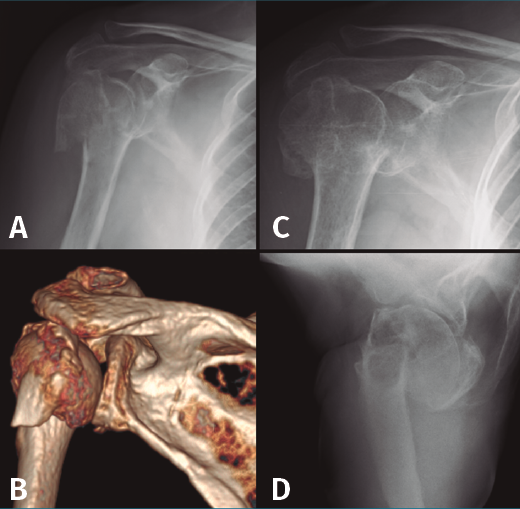

En el grupo que estamos analizando de pacientes en edad laboral con fractura compleja de húmero proximal su aplicación es limitada. Solamente quedaría indicado probablemente en pacientes mujeres mayores de 60 años con fracturas de 3 o 4 partes no muy desplazadas, con mala calidad ósea, un trabajo sin grandes requerimientos físicos y una vida extralaboral no muy activa (Figura 2). En estos pacientes la inmovilización con un cabestrillo de 4-6 semanas y la posterior rehabilitación funcional constituyen el tratamiento habitual.

Figura 2. Evolución radiológica del tratamiento conservador de una fractura de húmero proximal derecho. A: radiología simple anteroposterior; B: reconstrucción de la tomografía computarizada de la fractura de 4 partes desplazada; C y D: evolución radiológica del tratamiento conservador.